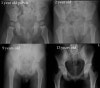

소아의 골반, 고관절, 대퇴골의 X-ray

- Pelvis AP view

4. Pelvic development

Hip bone ossifies from 8 centres.

At birth, the three primary centers are separate.

7-8yrs, the inferior rami of the pubis and ischium are almost completely united by bone.

Acetabulum achieve radiographic closure around age of 18 Iliac crests fuse in late 20’s.

Greater trochanter fuses at around age 14.

Femoral epiphysis fuses at around 14 for girls and 16 for boys.